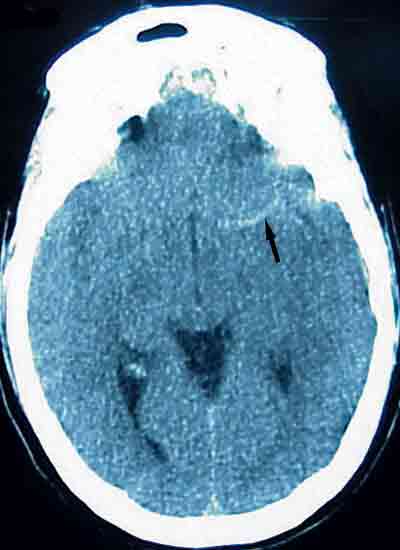

A 36-year-old man who had collapsed and sustained a bruised right shoulder was brought to the emergency department with acute emesis, cephalgia, blurred vision, aphasia, and right hemiparesis. The initial CT scan of the brain revealed a linear hyperdensity in the region of the left middle cerebral artery, indicating thrombus formation. An area of cerebral edema was noted with a small effacement from left to right. The patient had an internal carotid artery dissection.

Image courtesy of Christopher J. Pham, DO and Clark J. Okulski, DO.